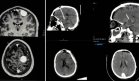

El abordaje diagnóstico incluyó ecografía dinámica de cadera que demostró engrosamiento del tensor de la fascia lata derecho (4 mm), alteración del patrón fibrilar y protrusión tendinosa sobre el trocánter mayor durante la evaluación dinámica, acompañado de chasquido audible y palpable.

La resonancia magnética complementaria mostró edema bilateral de la banda iliotibial y leve engrosamiento de la misma en el lado derecho (2.3 mm).

La ecografía dinámica emerge como la modalidad diagnóstica más útil, permitiendo visualizar en tiempo real el engrosamiento de la BIT (>4 mm en nuestro caso), la heterogeneidad de su ecogenicidad y, fundamentalmente, la subluxación tendinosa sobre el trocánter mayor durante maniobras de flexión y rotación externa de cadera.

Estos hallazgos dinámicos, correlacionados con el "chasquido" audible y la sintomatología dolorosa, son patognomónicos del SCRE. La resonancia magnética complementa la evaluación al demostrar edema de la BIT (>2 mm), cambios inflamatorios bursales y, en casos crónicos, atrofia ipsilateral del glúteo mayor.

En este caso (Roger David Medina-Ramírez et al), la ecografía dinámica resultó determinante tanto para el diagnóstico inicial como para evaluar la recurrencia postquirúrgica, donde mostró un mayor engrosamiento tendinoso (7.5 mm) y líquido peritendinoso.

La RM preoperatoria corroboró estos hallazgos, aunque con menor sensibilidad para captar el componente dinámico.